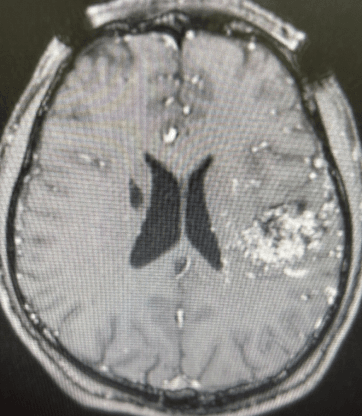

病例分享

病例,患者男性,26岁,2018年因癫痫发现脑动静脉畸形,行介入栓塞治疗。因仍有癫痫发作,来我院要求伽玛刀治疗。